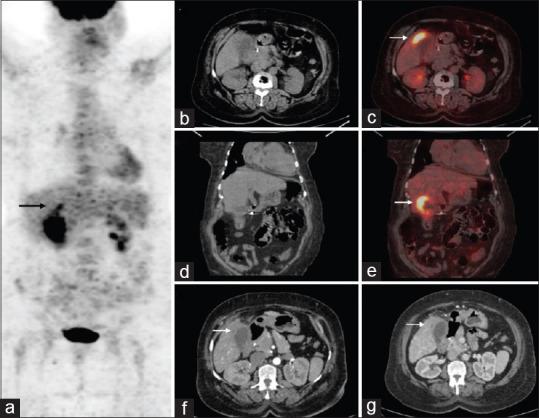

Xanthogranulomatous cholecystitis mimicking gallbladder cancer on F-fluorodeoxyglucose positron emission tomography/computed tomography scan.

The abnormal thickening of the gallbladder (GB) wall can be caused by a malignant condition like gallbladder carcinoma or by benign lesions such as chronic cholecystitis or xanthogranulomatous cholecystitis (XGC). Mural thickening is a common finding between them as fluorodeoxyglucose (FDG) can be taken up by inflammatory cells also. Here, we present a patient with irregular thickening of the GB wall which was suspected to of GB carcinoma since FDG positron emission tomography/computed tomography scan showed increased tracer uptake in the lesion. However, after surgery the histopathological report was suggestive of XGC.